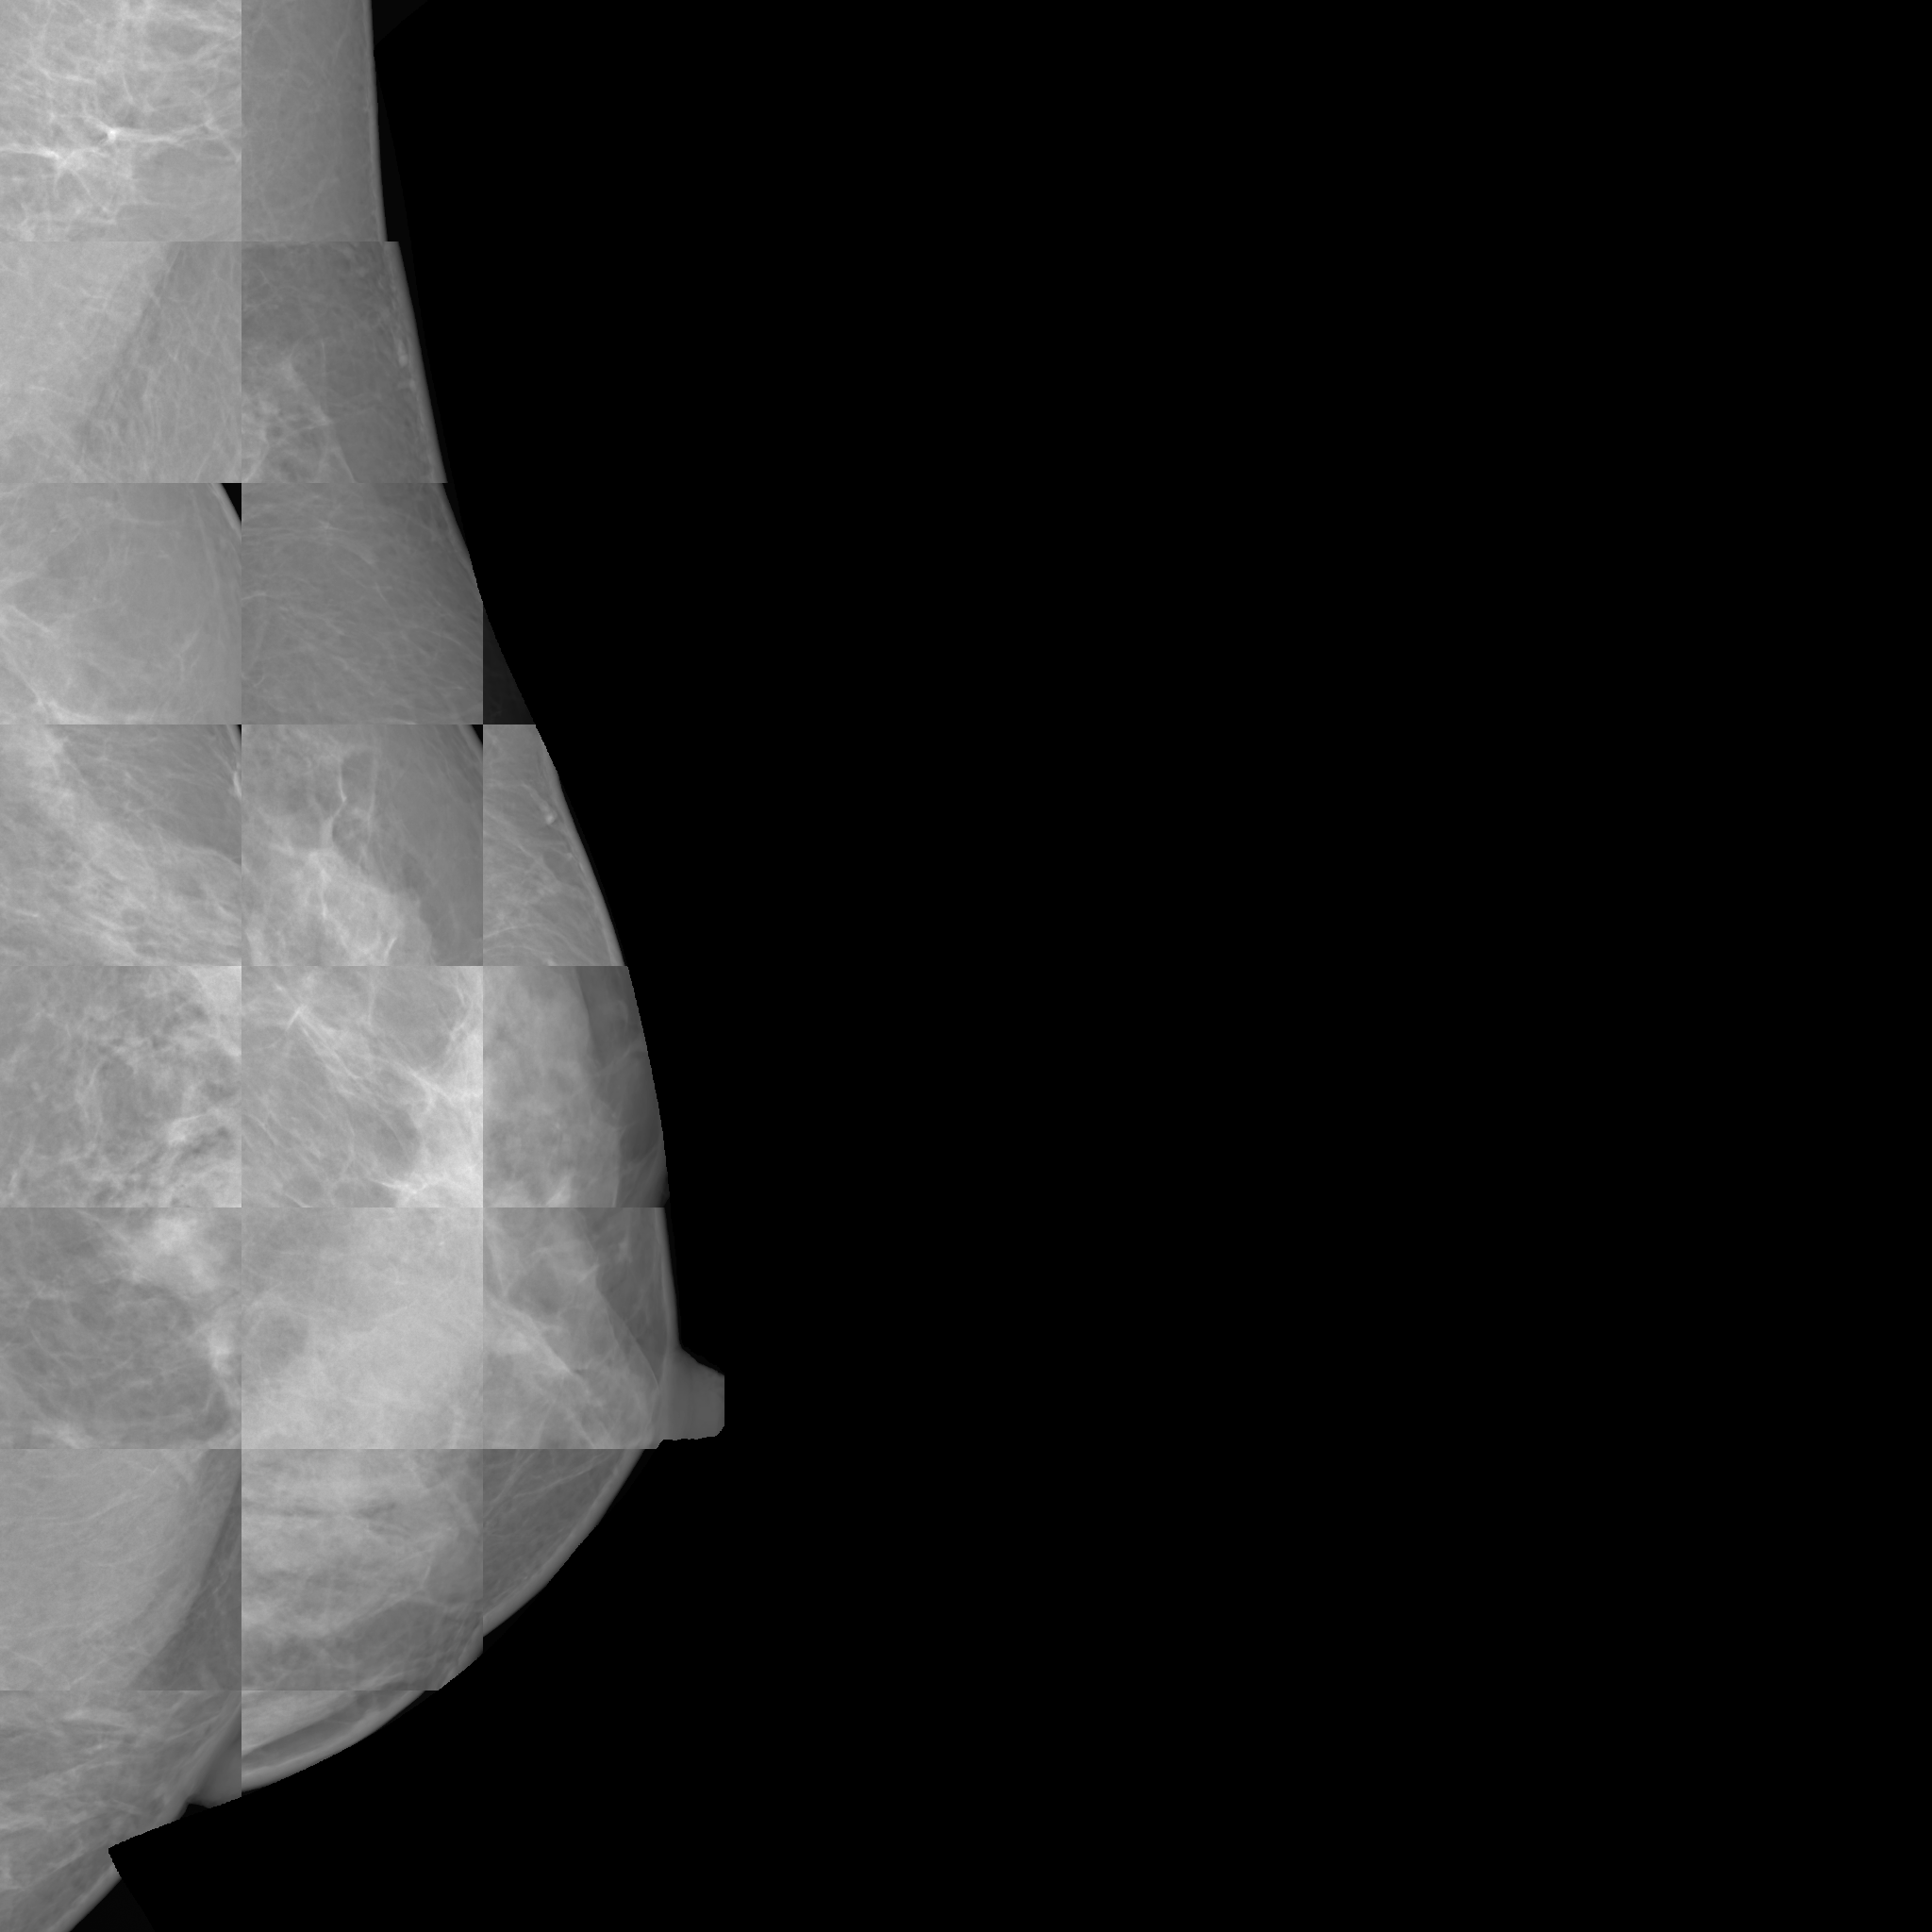

To overcome these challenges, this paper introduces MAMmography ensemBle mOdel (MAMBO), a novel approach that leverages an ensemble of diffusion models to generate mammography images at their native resolution. MAMBO uses a patch-based approach for generation which is conditioned both on local and global (full-image) context. In a nutshell, MAMBO involves the development of three distinct models: the first generates “standard”-resolution ( pixels) images to provide global context; the second increases the resolution to create local context for the target patch; and the third combines the outputs of both models to guide the generation of high-resolution patches, which are then reconstructed into a full-resolution synthetic mammogram. An example of a synthetic image generated by MAMBO is shown in Fig. 1. The image presents details at multiple resolutions, corresponding to the global and local contexts, and individual patch at full resolution. To the best of our knowledge, this is the first work to propose a diffusion model approach for generating very high-resolution synthetic mammograms.

This leads to a patch-based DDPM model based on the standard, three-channel U-Net architecture, within which the context information is provided at two scales (global and local) using the additional input channels, as shown in Fig. 2:

where represents the generated patch, and and represent the global and local context, respectively. This model can be readily used to create high-resolution mammograms that are visually indistinguishable from the original.